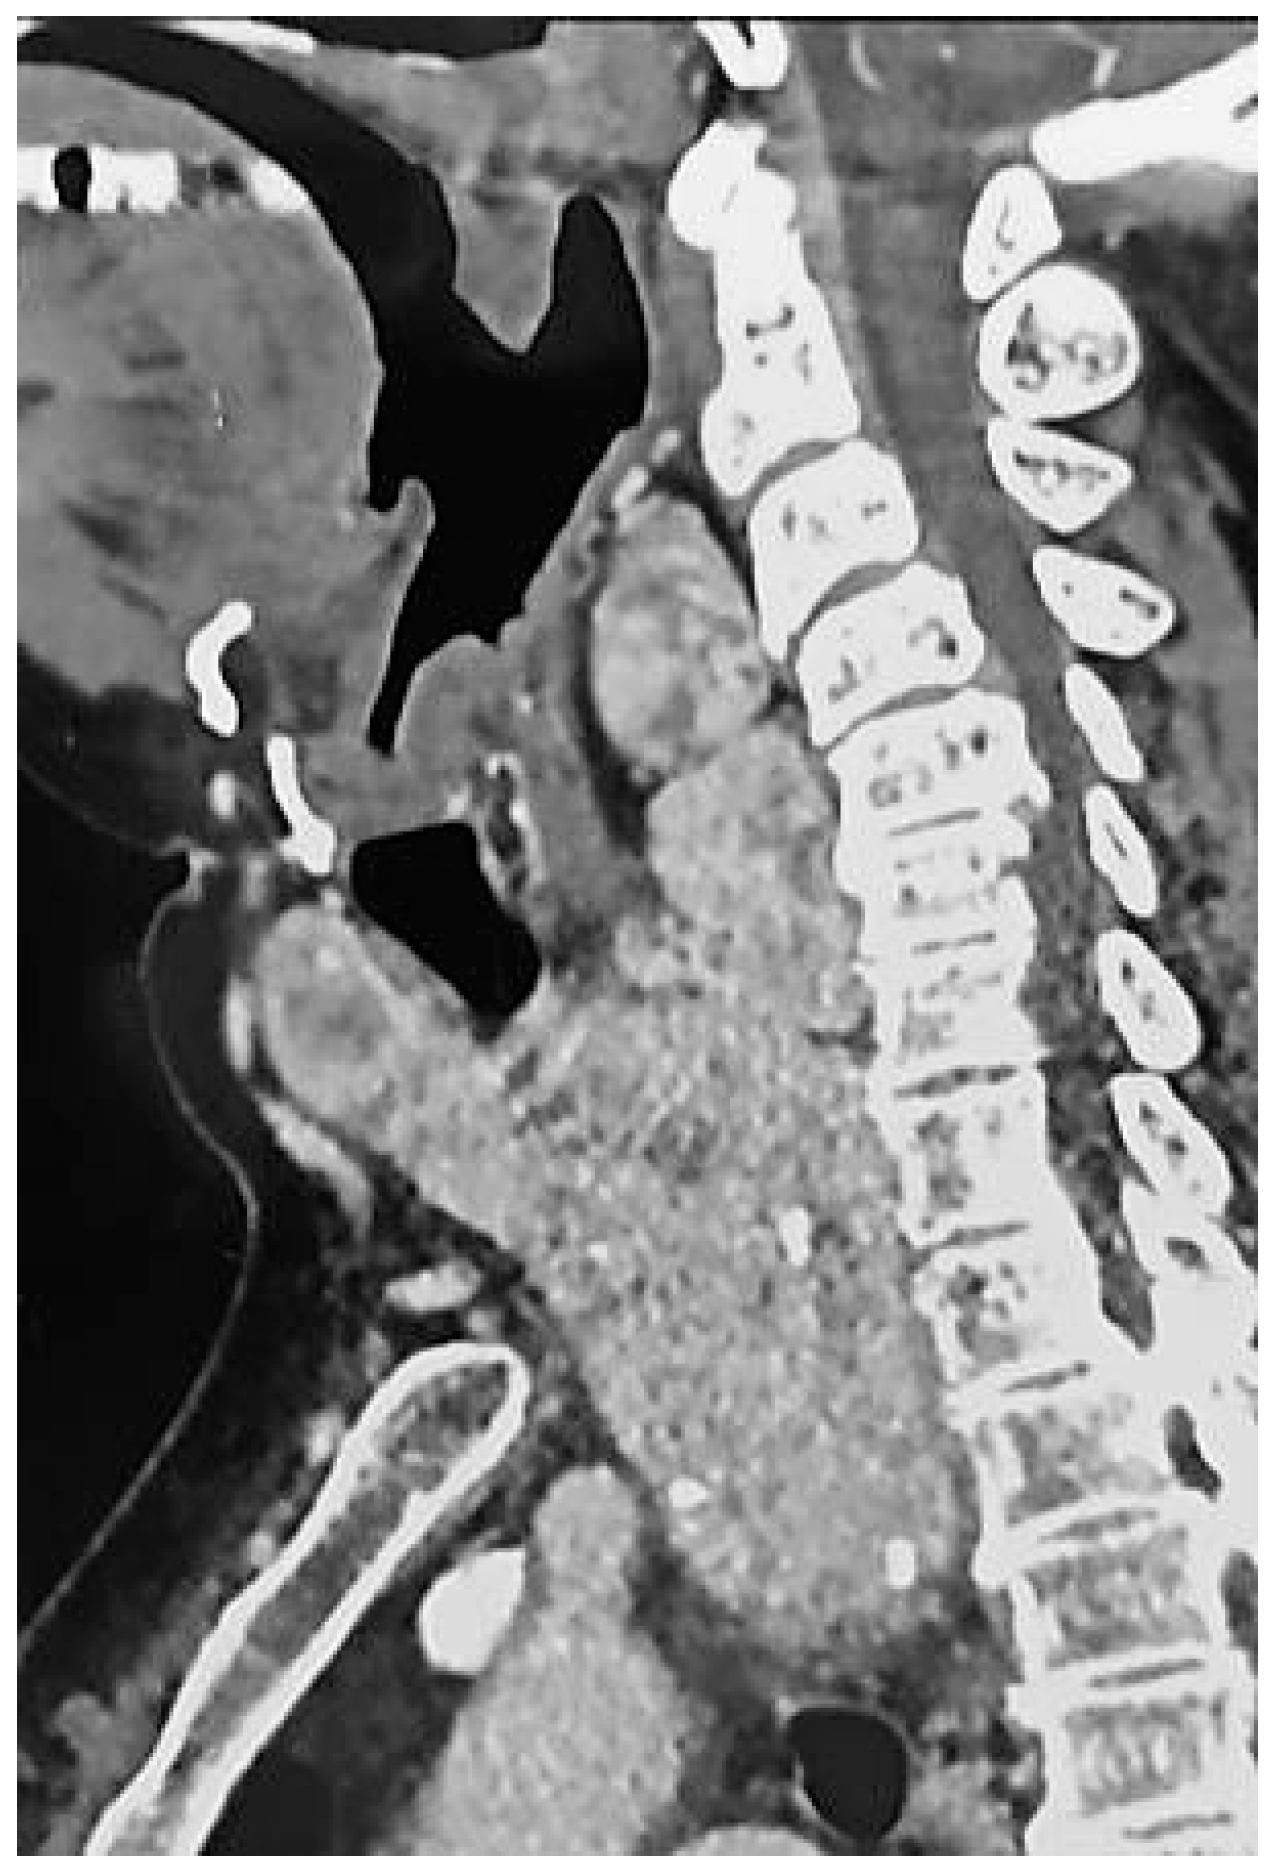

2. Case Description